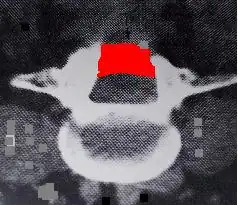

CT scan of laminectomy showing scar formation (highlighted in red)causing new stenosis.

Spinal stenosis can be a late complication after laminectomy for disc herniation or when surgery was performed for the primary pathological condition of spinal stenosis.[11][73][74] In the Maine Study, among patients with lumbar spinal stenosis completing 8- to 10-year follow-up, low back pain relief, predominant symptom improvement, and satisfaction with the current state were similar in patients initially treated surgically or non-surgically. However, leg pain relief and greater back-related functional status continued to favor those initially receiving surgical treatment.[75]